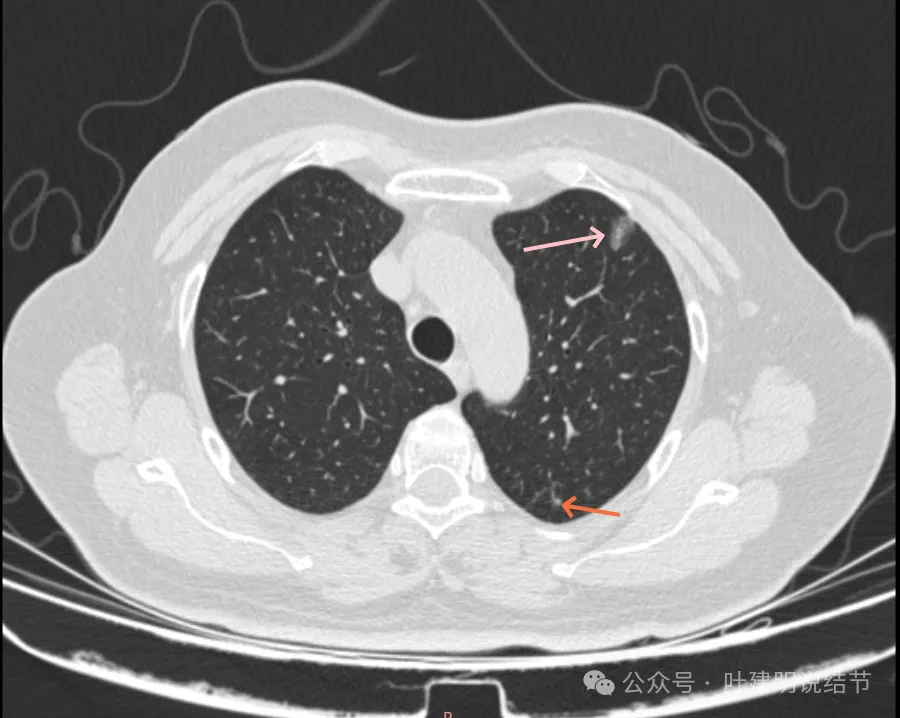

病灶5-6:左肺尖淡磨玻璃结节,轮廓较清。

病灶33:右上叶磨玻璃结节,考虑不典型增生或原位癌可能性较大,总体风险仍低。

病灶34:左上叶淡磨玻璃结节,轮廓较清,有小血管贴着病灶,似乎有进入穿行的。

病灶35:右上叶淡磨玻璃结节,轮廓较清。

病灶36-37:淡磨玻璃结节,轮廓较清。

病灶41-43:左下叶多发结节,密度淡,桔色的病灶似乎有小空泡征的样子,但密度很低。